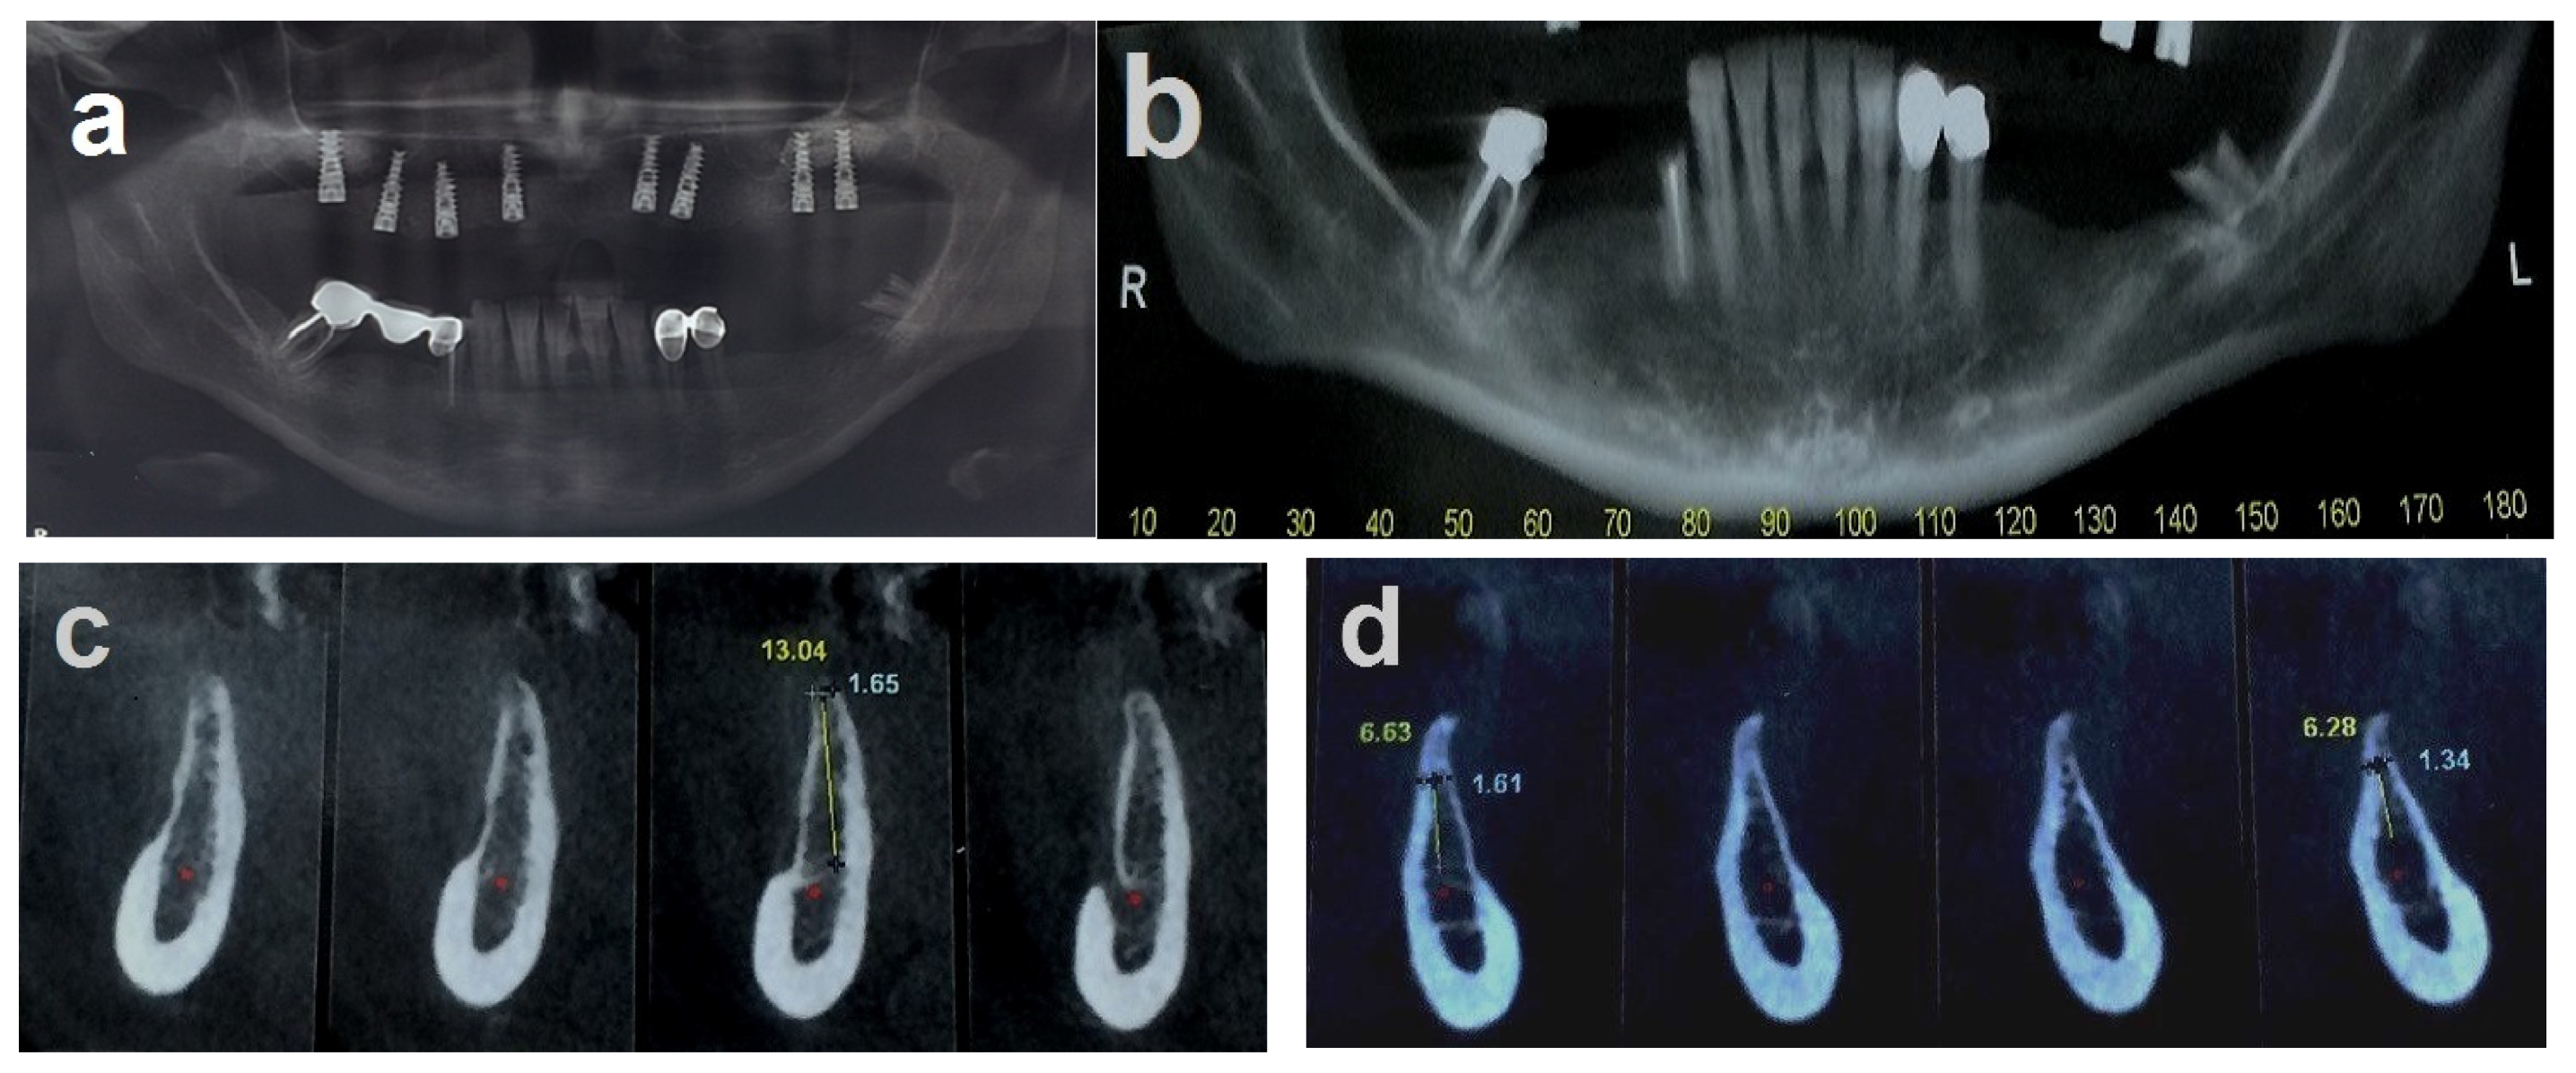

A 36-year-old woman was referred for bone augmentation and dental implant placement in the atrophic posterior mandibular ridges. The examination revealed partial edentulism of the mandible, with missing posterior teeth on both the right and left sides (Figure 6a). Computed tomography confirmed a significant horizontal bone deficit in the posterior mandibular regions bilaterally (Figure 6b,c). A two-stage treatment approach was planned. In the first stage, the honeycomb bone (HCT) technique was employed to augment the right and left posterior mandibular regions.

Figure 6.

(a) Bilateral posterior mandibular edentulism. (b,c) Computed tomography showing severe horizontal atrophy with knife-edge residual ridges. (d) The bone block harvested from the retromolar donor site. (e,f) The harvested bone block and its subsequent splitting, resulting in thin bone blocks and cortical wedges. (g) The bone augmentation procedure: grooves were created using high-speed at the recipient site, followed by the insertion and tapping of the cortical bone wedges into the grooves. (h,i) A thin bone plate is positioned over the bone wedges and secured with screws, creating bone compartments resembling a honeycomb. (j) Right side. (k) The bone compartments are filled with allogenic particulate bone graft to achieve the desired graft volume on the right side. (l,m) Double-layer, tension-free closure of the recipient sites performed using BFFGs. (n–q) CBCT scan, four months postoperatively show significant bilateral horizontal bone gain. (r) Two implants were placed on the right side and four implants on the left side. (s) Panoramic view at 8-year follow-up. (t–v) CBCT scans taken 10 years after implant placement reveal stable augmented bone levels. (w) Eleven-year follow-up periapical x-ray of the left side, demonstrating no significant marginal bone loss. (x) 3 mm of marginal bone loss observed at the mesial implant. The yellow arrows show the cortical wedges that remain visible at the recipient sites.

In May 2013, a cortical bone block was harvested from the right retromolar area (Figure 6d). The harvested block was then split, yielding two thin bone blocks and multiple bone wedges (Figure 6e,f). The recipient sites were prepared by creating grooves, into which the bone wedges were inserted in a stable position bilaterally (Figure 6g). Two thin bone blocks were then secured over the bone wedges using screws. This configuration resulted in multiple bone compartments resembling a honeycomb structure (Figure 6h–j). After trimming any sharp edges, the compartments were filled with particulate allograft bone substitute, achieving the desired final bone volume (Figure 6k). The augmented sites were then covered with a resorbable membrane and a free buccal fat pad graft (BFFG) before being closed in a tension-free manner (Figure 6l,m). The healing process was uneventful throughout the follow-up period. A CBCT scan performed four months postoperatively, in September 2013, confirmed significant horizontal bone gain of 4–6 mm (Figure 6n–q). Upon reentry under local anesthesia, the newly formed bone volume was evident, with the bone wedges fully integrated into the regenerated bone mass. Six dental implants were successfully placed (Figure 6r). After three months, all the implants had achieved full osseointegration, allowing for final prosthetic rehabilitation. This case has been followed for 11 years. A panorex obtained at 8 years showed implants without marginal bone loss (Figure 6s), and a CBCT scan obtained in September 2023 demonstrated stable bone volume 10 years post-surgery, with no resorption of the augmented bone blocks (Figure 6t–v). Periapical radiographs taken in July 2024 further confirmed the long-term stability of the outcomes and implant survival. At this time, the first implant on the right side showed a 3mm marginal bone loss, possibly due to food impaction from a decayed adjacent premolar. The remaining five implants exhibited no signs of marginal bone loss. The cortical wedges remained visible at the recipient sites in both figures (Figure 6w,x).